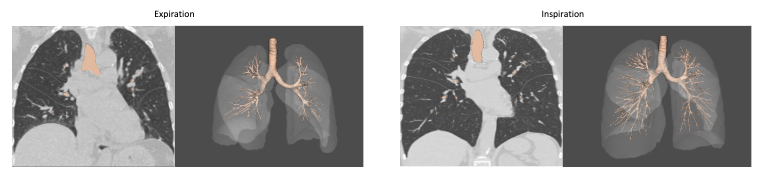

Building on this foundation, a recent study by Chen et al., published in 2024 in European Radiology, examined how inspiratory volume levels affect airway and vascular measurements in adult COPD patients. Notably, the study used Thirona’s LungQ Bronchial-Artery (BA) software, highlighting the critical value of consistent lung volume for quantitative imaging analysis in adult populations as well.

Side-by-side comparison of CT scans at inspiration and expiration, including corresponding AI-based analysis using LungQ-BA. The images demonstrate how differences in lung volume impact airway detection and measurements, influencing the number of visible bronchi and the resulting analysis outcomes.